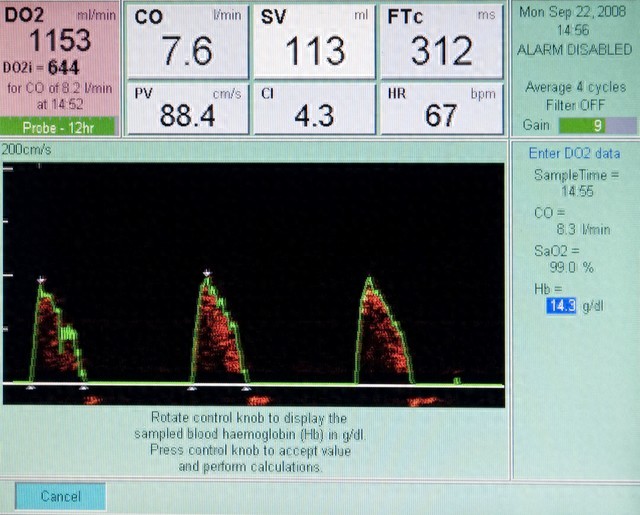

做心脏超声,能清楚看到心肌的厚度、心室的大小、心脏的收缩和舒张功能,还能排查有没有心室肥厚、瓣膜反流这些问题。早发现,就能早干预,避免小问题拖成心肌缺血、心衰的大麻烦。

我之前有个 40 岁的患者,低压常年 95 左右,总说胸口发闷,一开始没当回事,后来做心脏超声发现心肌已经轻度肥厚了。赶紧调整生活方式,配合中药调理,半年后低压降到 85,复查心脏超声,心肌厚度也恢复了正常。